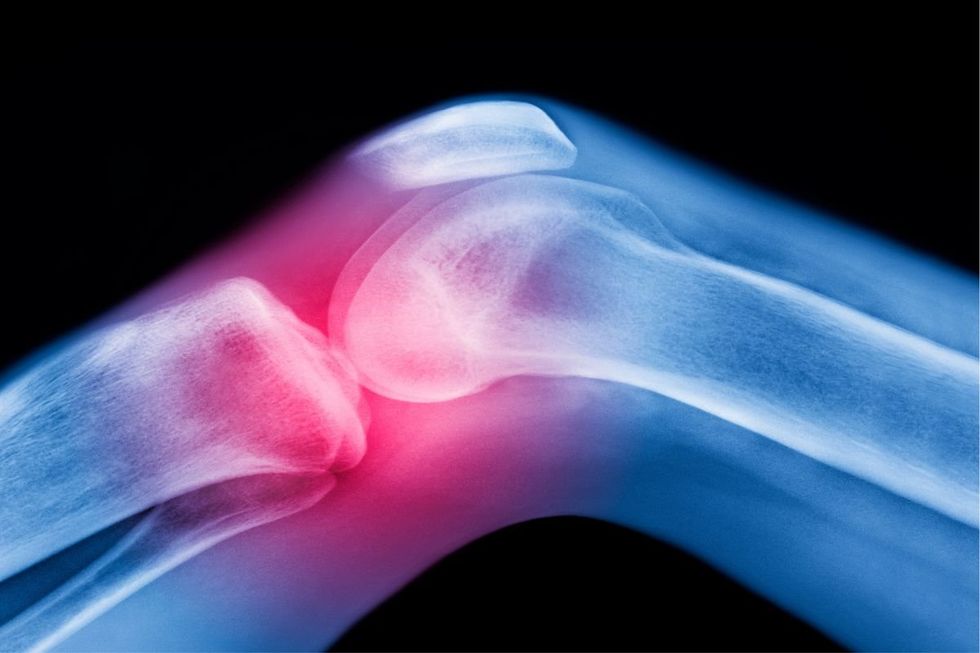

Osteoarthritis causes persistent discomfort and rigidity in the joint

|GETTY

The condition causes persistent discomfort and rigidity in the joints, making routine activities increasingly challenging for those afflicted.